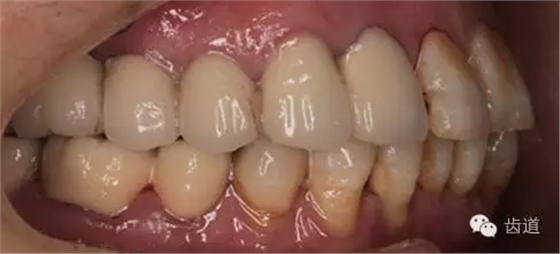

1、全口正面觀

1、治療前

2、治療后